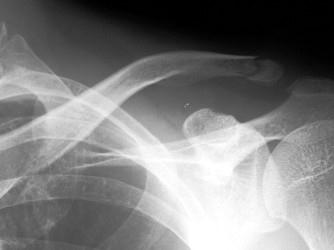

男,25岁,外伤后摄片,请结合影像图像选择最可能的诊断 ( )A、肋骨骨折伴气胸B、锁骨骨折伴气胸C、锁骨骨折D、原发性气胸E、肋骨骨折

问题 男,25岁,外伤后摄片,请结合影像图像选择最可能的诊断 ( )

选项 A、肋骨骨折伴气胸 B、锁骨骨折伴气胸 C、锁骨骨折 D、原发性气胸 E、肋骨骨折

答案 C